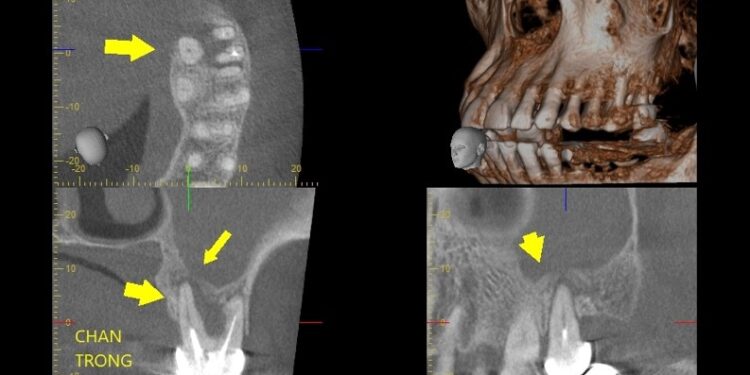

Hình 2. Đường thông giữa ổ viêm chân răng với xoang hàm trên phim chụp Conebeam CT

– Chẩn đoán hình ảnh: hiện nay chủ yếu chỉ định phim chụp cắt lớp vi tính mũi xoang và chụp Conebeam CT, giúp đánh giá đồng thời đặc điểm bệnh lý của xoang hàm và răng liên quan, đồng thời là bản đồ để bác sĩ lập kế hoạch can thiệp hiệu quả.